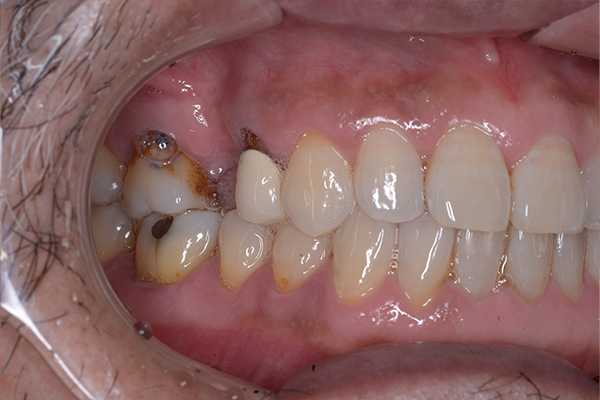

治療前〜治療後のレントゲン写真

患者様の要望過去に治療したブリッジを外し咬み合わせの平面を整えて、被せ物や詰め物を綺麗にしたい。

治療期間10ヶ月

治療費用1,600,000円

治療内容インプラント2本、アンカースクリューを用いた部分矯正、

セラミックによる補綴治療

治療のリスクセラミックの破折の可能性